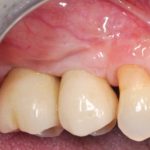

Autotrapianto di ottavo incluso a sostituzione di un settimo irrimediabilmente compromesso: case report

I trapianti dentali sono un capitolo...